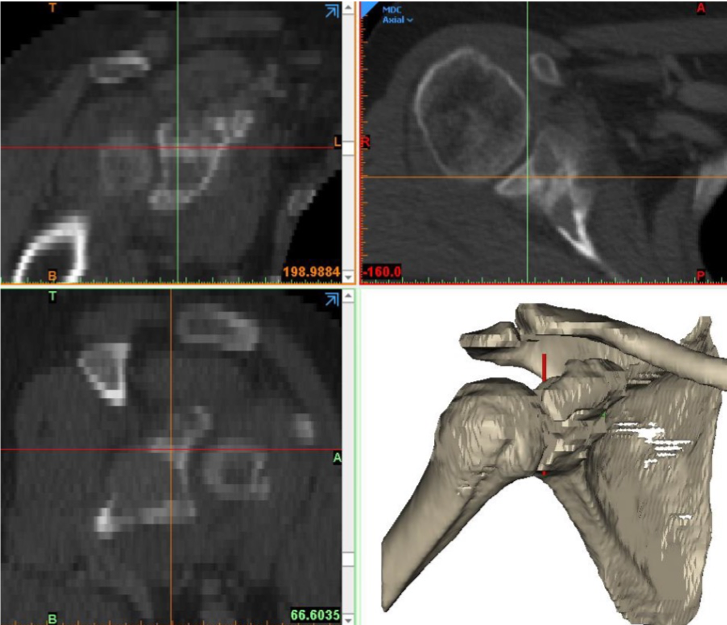

Pre-op

- 60 year-old patient

- Sarcoma of right scapula

Concept proposal of customLINK department

- Total scapula replacement, right side, made of Ti6Al4V, with TrabecuLink structure

- Glenoideal head, 22 mm diameter, made of Ti6Al4V with hypoallergic PorEx coating (TiNbN)

- Scapular replacement with special TrabecuLink filling for promotion of connective tissue attachment